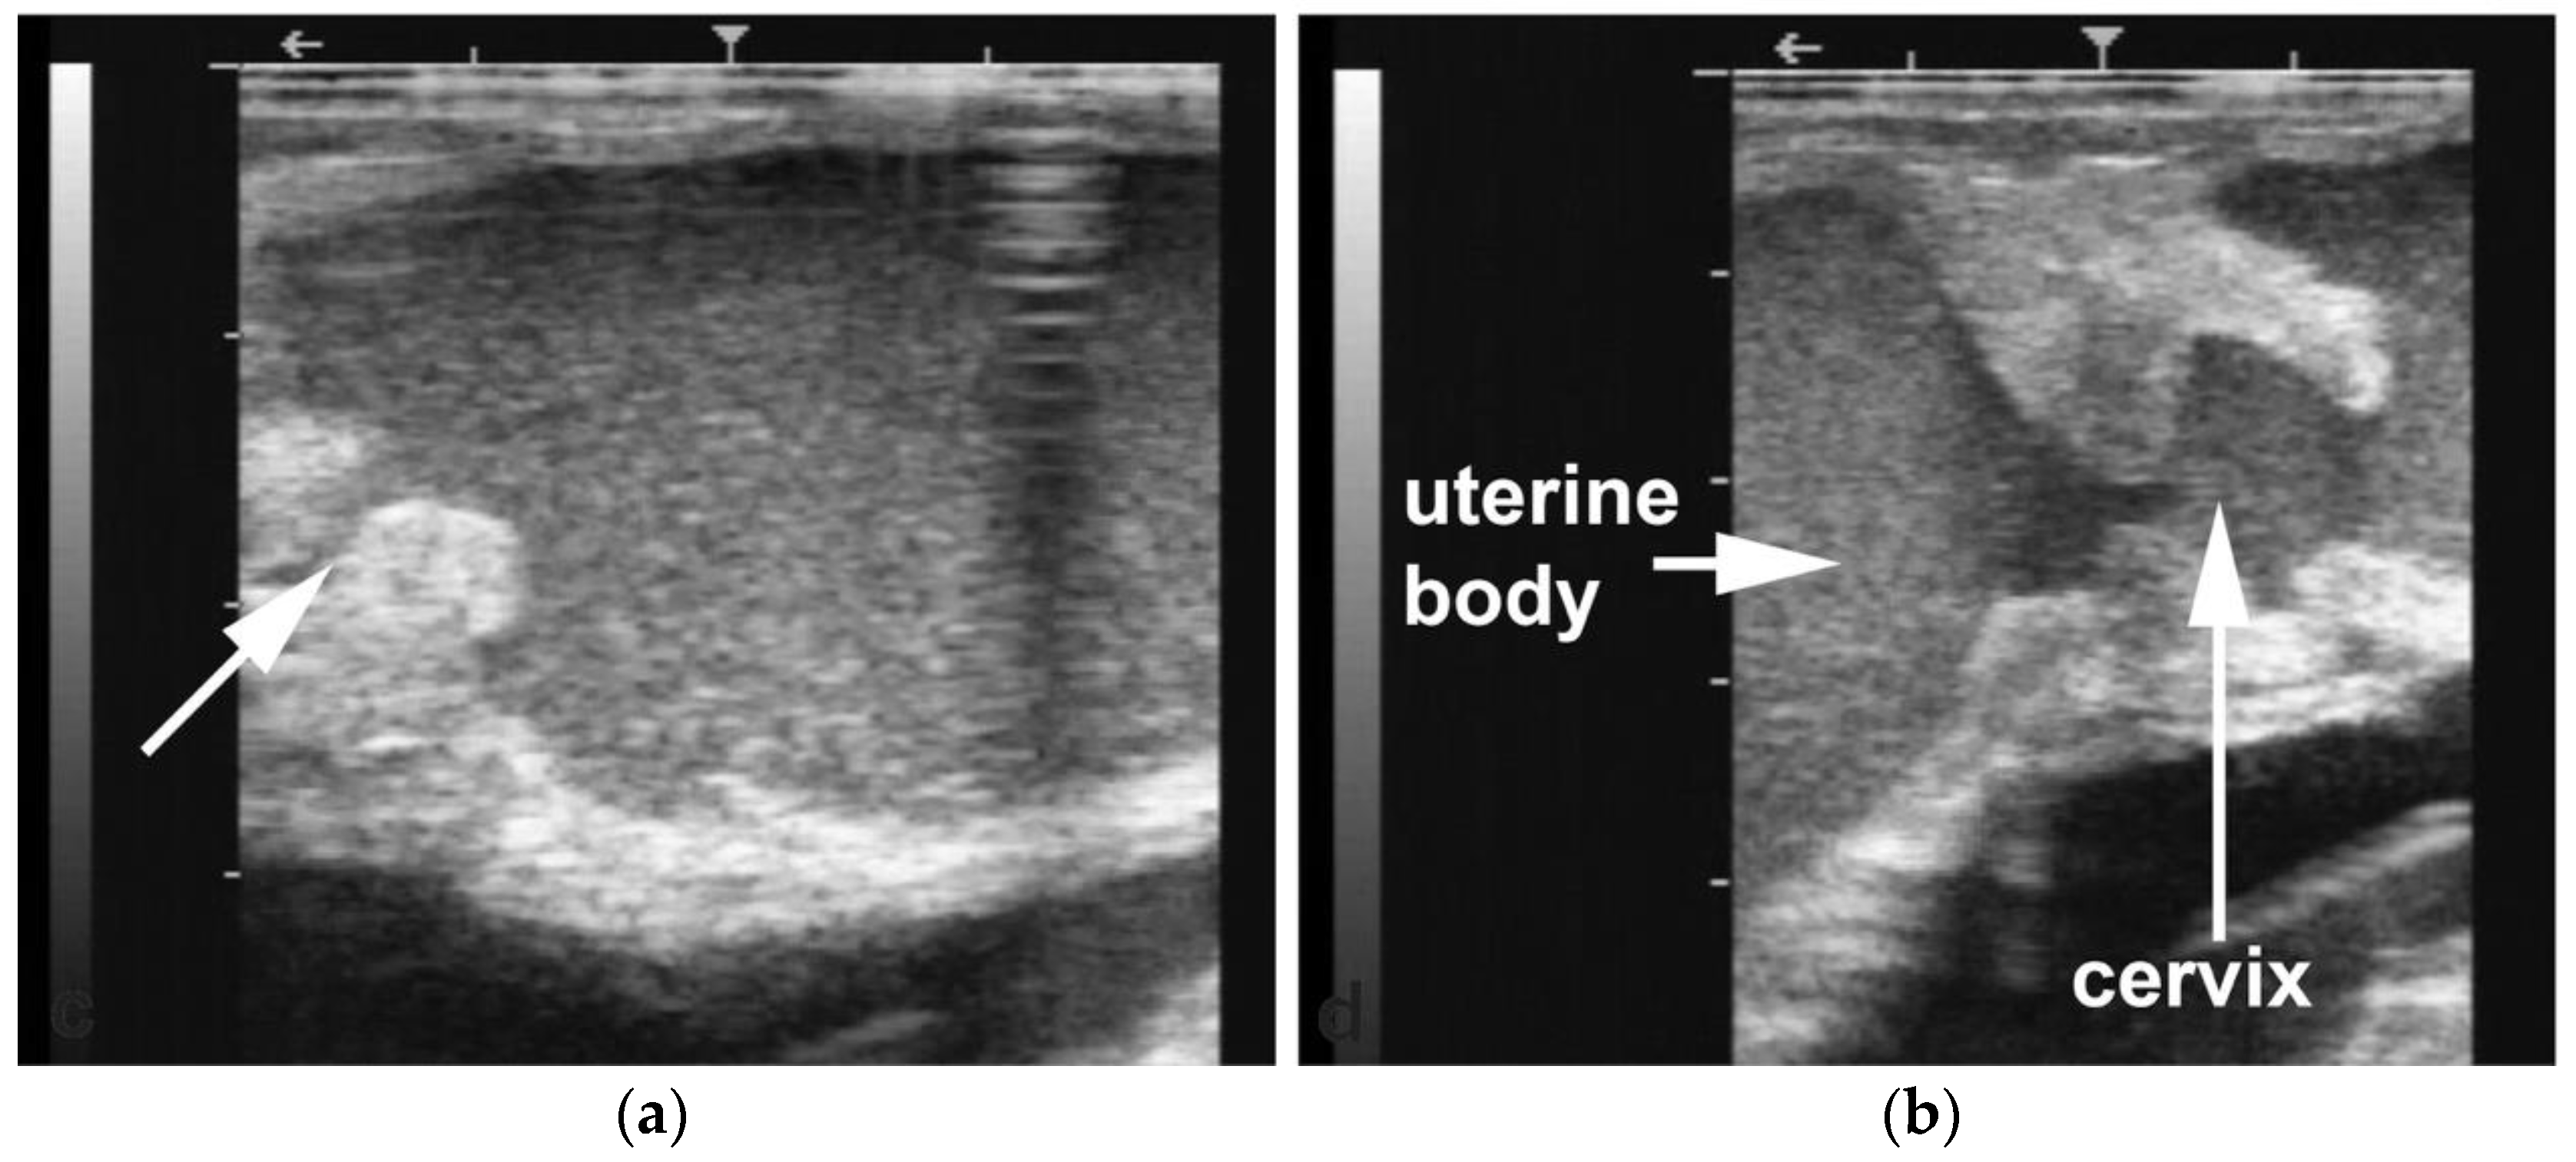

Pyometra and non-congenital mucometra are often due to cervical or vaginal adhesions resulting from poor handling of dystocia or fetotomy [7,14,63]. Uterine cysts and intraluminal adhesions have also been observed following dystocia or postpartum uterine prolapse (Figure 13).

Figure 13. Gross pathology (scale bar: 1 cm) and ultrasonogram of intraluminal uterine cysts due to intraluminal uterine adhesions in an alpaca.